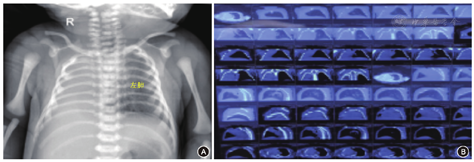

转入后体格检查:体温36.2℃、心率150次/min,呼吸48次/min,血压62/27 mmHg(1 mmHg=0.133 kPa),平均动脉压40 mmHg;足月儿貌,反应可,哭声响亮,全身皮肤无黄染;唇无发绀,颈软,未见三凹征,左肺可闻及散在湿啰音,右肺未闻及明显呼吸音。入院诊断:(1)新生儿肺炎;(2)先天性右肺缺如?;(3)心包积液?。予以抗感染、预防出血鼻导管吸氧等处理。该患儿鼻导管给氧2 h,呼吸一直平稳,各项生命体征指标正常。生后2 d患儿胸部X射线片提示:右侧胸腔呈密度均匀致密影;左肺野透亮度增高,纵隔心影向右移位,右膈肌面显示不清,左膈肌面光滑,左肋膈角锐利。生后3 d行胸部CT扫描,在三个维度均显示右肺未发育(图3);诊断:先天性右肺缺如。超声心动图:心脏大部分位于右侧胸腔,心尖朝左;主动脉根部内径宽9 mm,左心房10 mm,左心室15 mm,室间隔厚3 mm,左心室后壁厚3 mm,右心房12 mm,右心室12 mm,肺动脉8 mm,左肺动脉内径3 mm;右肺动脉、静脉未显示,肺动脉峰值流速0.7 m/s;主动脉峰值流速1.1 m/s;二尖瓣:左心室舒张早期快速充盈的充盈峰(E峰)0.8 m/s,舒张晚期(心房收缩)充盈的充盈峰(A峰)0.7 m/s,E峰>A峰,左心室缩短分数40%,射血分数65%;心脏各房室内径大小正常,房间隔可见宽2.5 mm的连续中断,室间隔探及宽1.6 mm的穿隔血流信号,室间隔与左心室后壁运动正常;各瓣膜清晰,启闭正常,升主动脉、肺动脉位置和内径正常,降主动脉与肺动脉分叉处可见交通支,心包腔内未见明显异常回声(图4)。

注:R:右侧(Right)